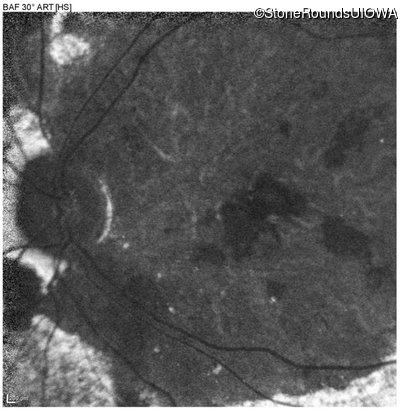

Blue Autofluorescence - Right - 20/250 sc

Exemplar

Blue Autofluorescence - Left - 20/300 sc